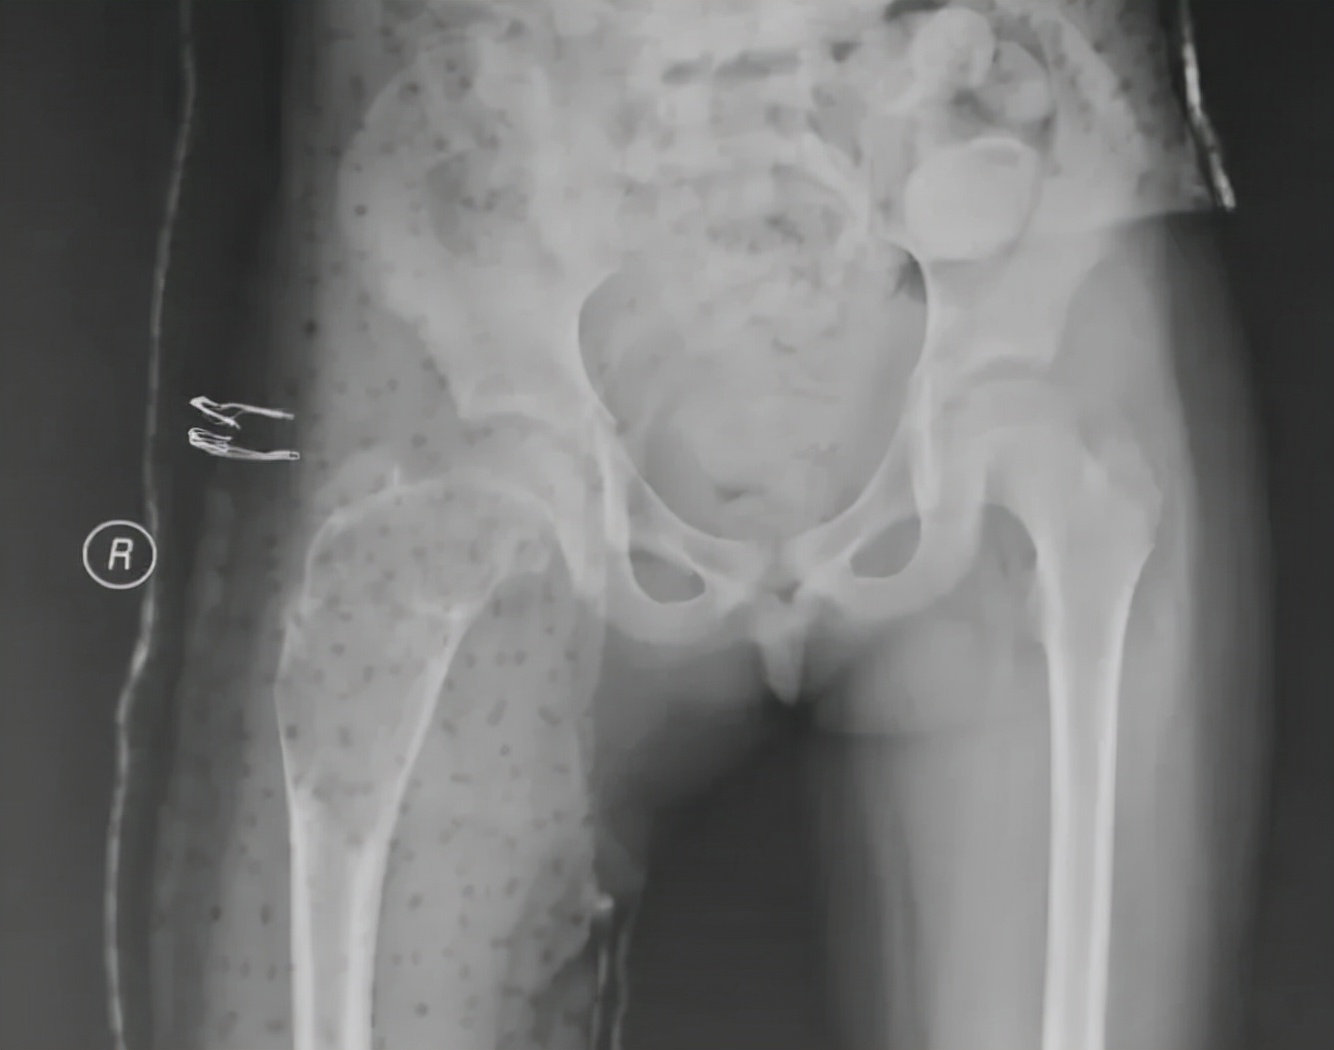

孩子上三年级,酷爱跳舞,获得过青少年舞蹈比赛一等奖,一天练习的时候,突然髋关节疼痛,站立困难,经当地医院拍片检查,提示股骨近端巨大的骨破坏引发的病理性骨折!按照孩子的话说,就是“从此告别了热爱和坚持的舞蹈!”遭此意外,对每个家庭而言,无异于灭顶之灾。

我接诊后,通过临床、影像和病理的综合研判,确诊为股骨近端动脉瘤样骨囊肿,这类疾病虽是良性肿瘤,但病变范围大,复发率高,破坏严重,对生长发育期儿童,可能导致肢体畸形、跛行等严重后果,若治疗选择不当,更会导致雪上加霜。经过慎重考虑,结合以往的病例治疗经验,我采用了微创的治疗方法,手术后6周患儿即开始下地活动,术后3个月就逐步开始舞蹈训练了,孩子的梦想得以继续。

从影像学看,这个孩子手术后股骨近端留置多根钢针,术后2年左右的时间,尽管股骨强度有增加,但是骨囊肿还未愈合,并出现了部分退针的情况,孩子身高已经比第一次手术时长了近10cm了,选择什么样的治疗方案再次摆到面前,当我决定更换固定针,继续使用微创治疗理念时,患儿家长对于可能出现的针道激惹等并发症表示了完全的理解,并认真了解了术后相关的注意事项,正是因为家长的配合,手术之后患儿就能够进入快速康复。